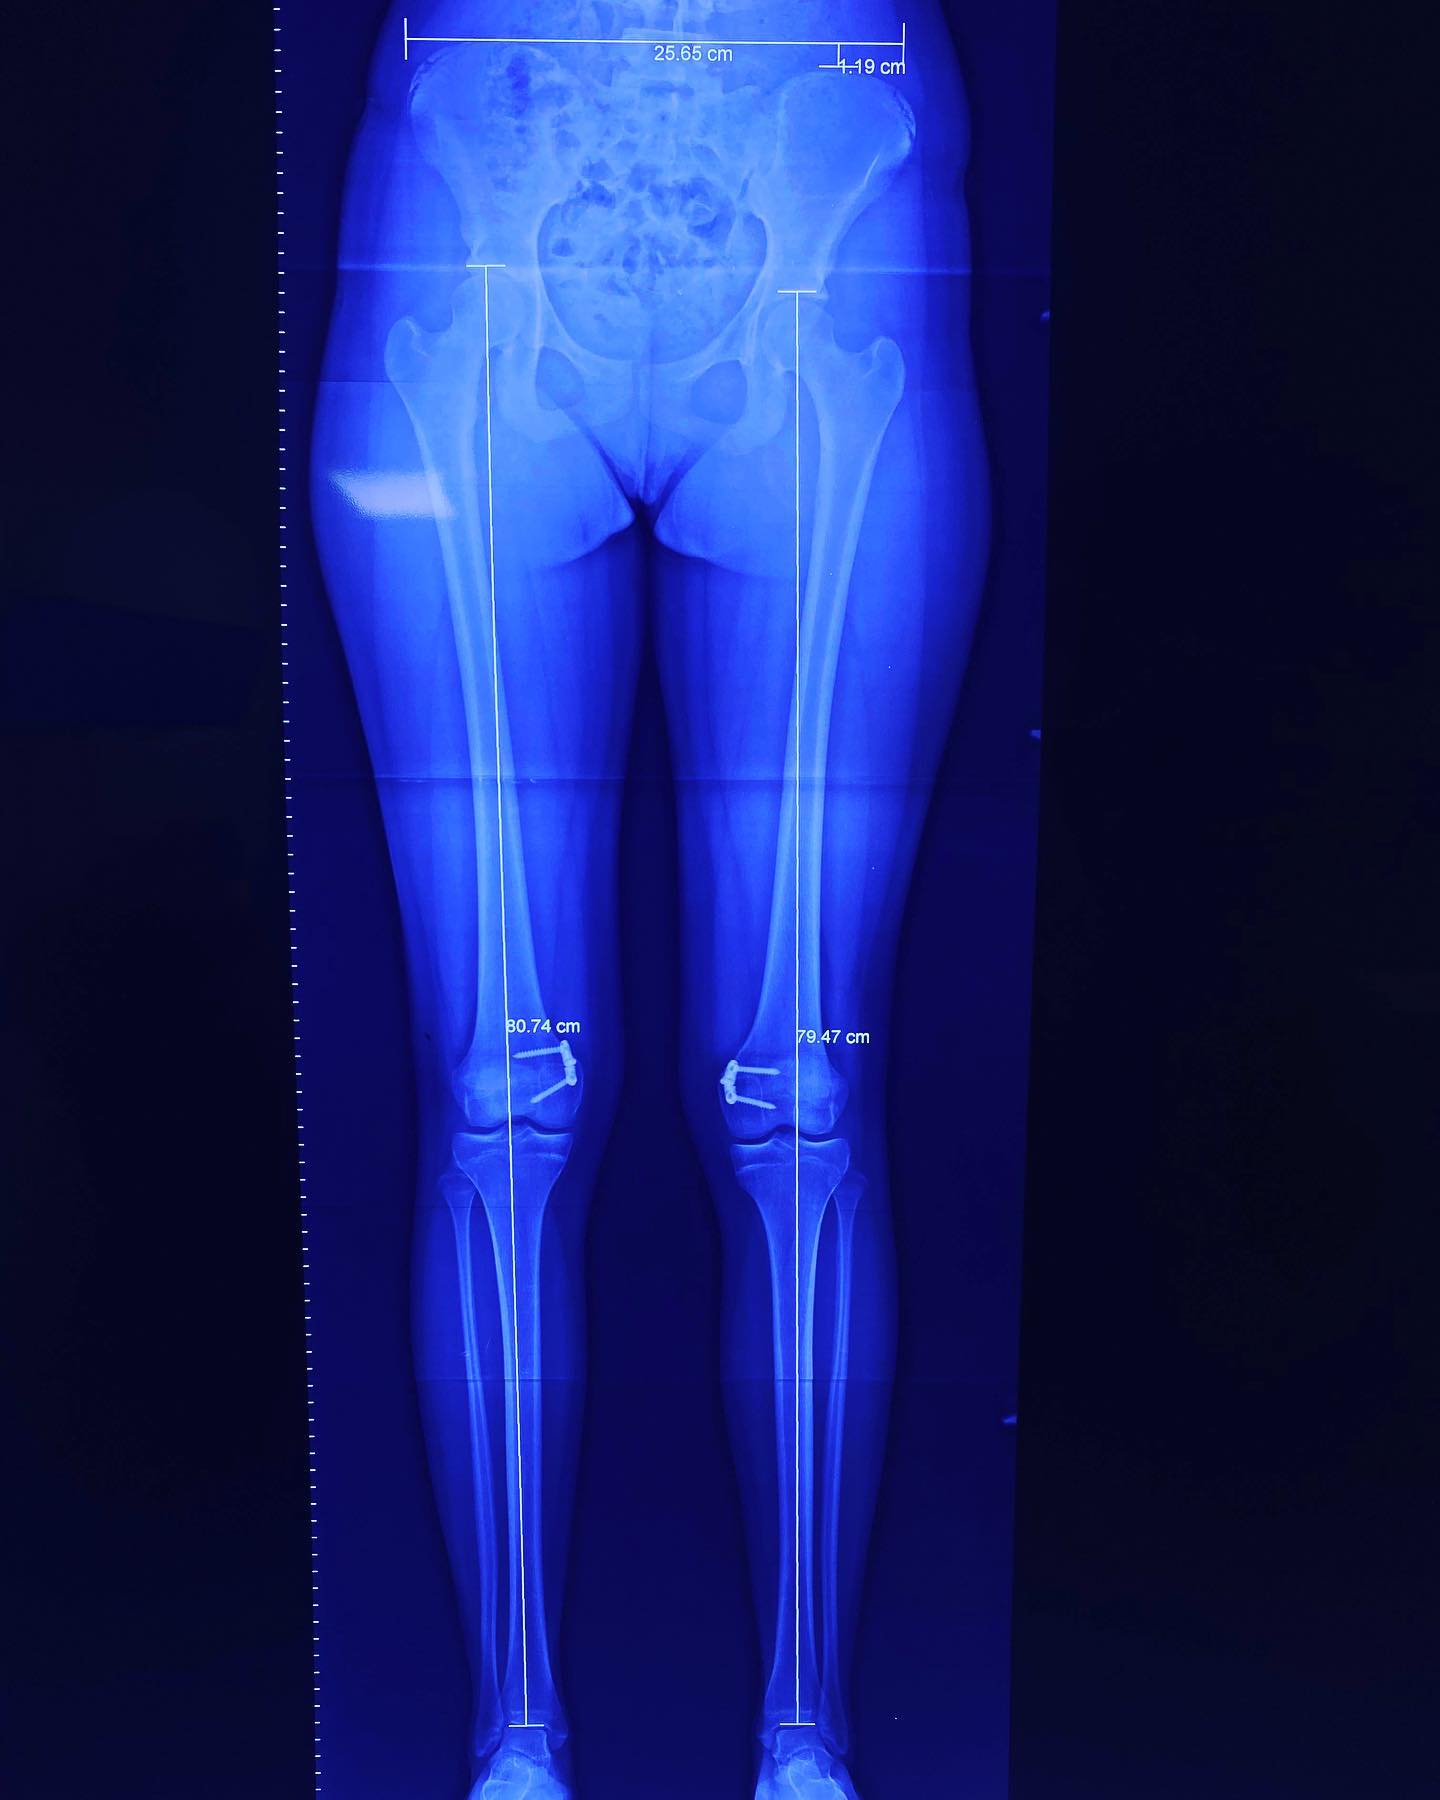

• Deformidades angulares en rodilla

Rodillas en valgo

También llamadas rodillas valgas o rodillas en varo, estas condiciones se refieren a la alineación de las piernas. Estas alineaciones pueden ser un estado natural del desarrollo de un niño o una niña hasta los 7 años de edad. Después de esta edad, ya no se consideran normales. Sin embargo, en algunos casos, esta deformidad puede aumentar hasta llegar a ser discapacitante y dolorosa, y es en ese momento cuando debe ser tratada.

Consulta y desarrolo de nuestros pacientes despues de ser intervenidos, lo que muestra la evolucion y avances desde la primera vez que nos visitaron